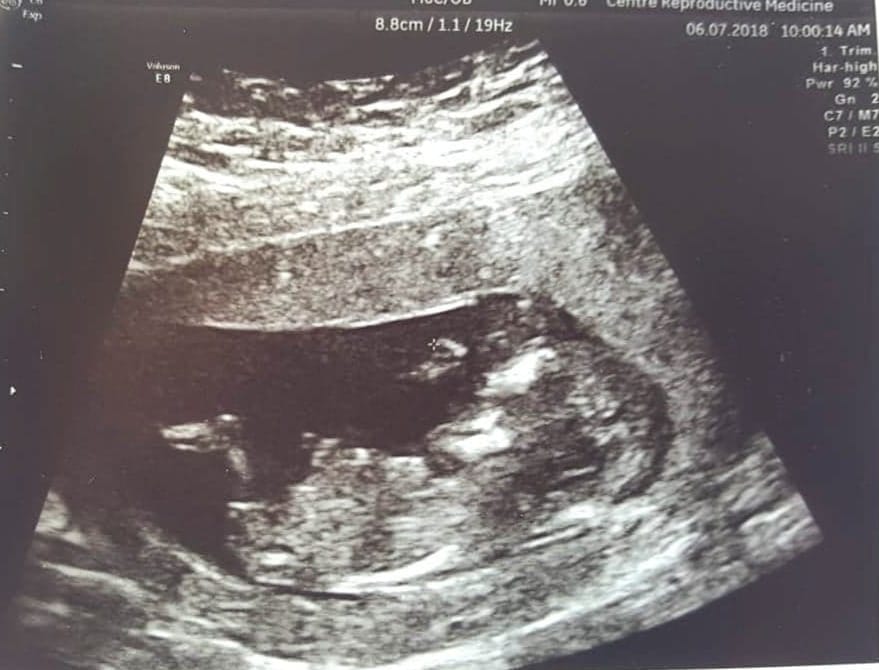

Update at 13.2 [emoji4]Attachment 39899Attachment 39900Attachment 39901